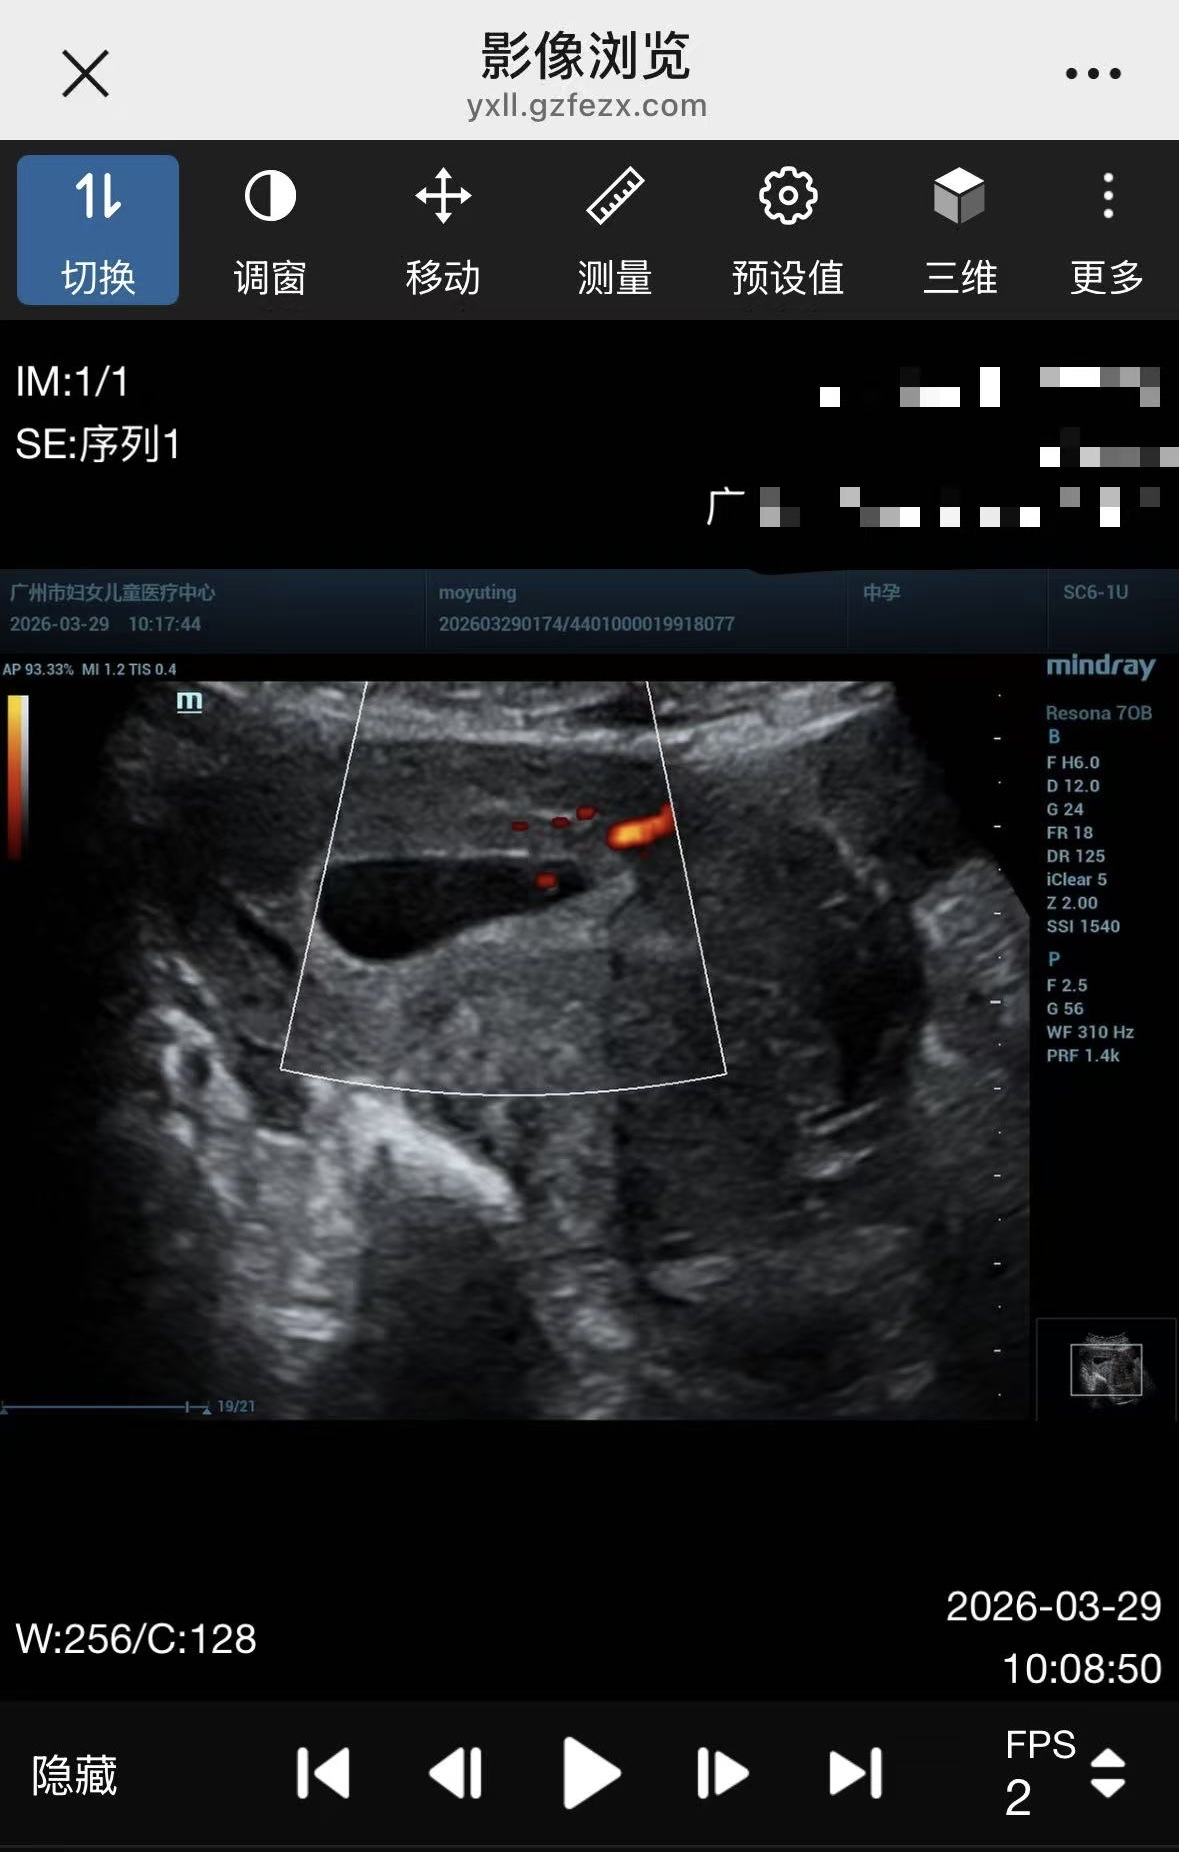

孕早期是妊娠期的第一关,要做好孕早期产检,确认是否宫内妊娠,筛查宫外孕,并检查孕酮。